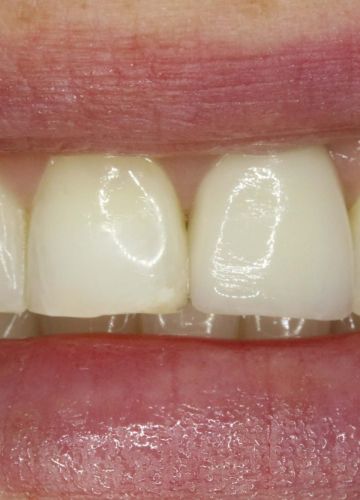

Slāņots cirkonija keramikas kronis + zoba implants

• Pēc 5 mēnešiem tika izgatavots slāņots cirkonijkeramikas kronis